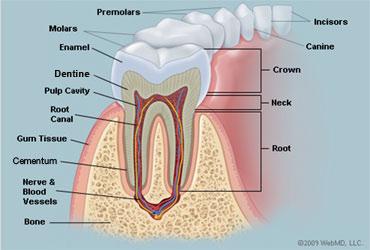

10

11

12

13

baby teeth

Permanent Teeth

Incisors (8)

16

Permanent Teeth

Premolars (8)

18

Permanent Teeth

Crown

Neck

Root

Alveoli

Gingiva

Enamel

Dentin

Cementum